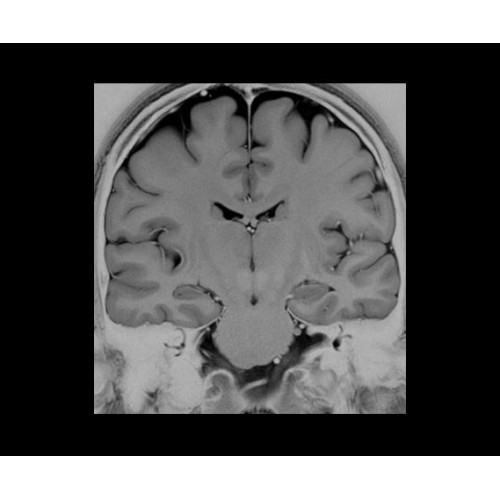

• Специальный пакет приложений для измерения и сравнения объемных изображений ЦНС с нормами поможет вам в диагностике нейродегенеративных заболеваний, а дополнительные инструменты визуализации — в постановке точного диагноза с помощью бета-амилоидов и радиоизотопных маркеров ФДГ.

• In vivo лаборатория — получайте полные данные биохимических процессов in vivo с мультиядерной спектроскопией на SIGNA PET/MR.